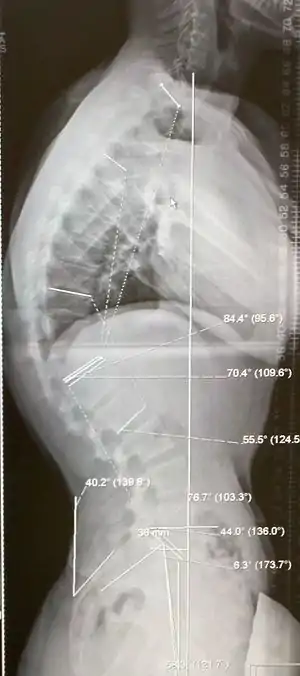

از آنجا که بیماری شوئرمان منجر به گوژپشتی میشود به آن «گوژپشتی شوئرمان» هم گفتهاند. در این بیماری، ستون فقرات نسبت به سطح پیکانی sagittal plane رشدی نامتقارن دارد یعنی زاویه قدامی (جلویی) آن بزرگتر از زاویه خلقی (عقبی) است.